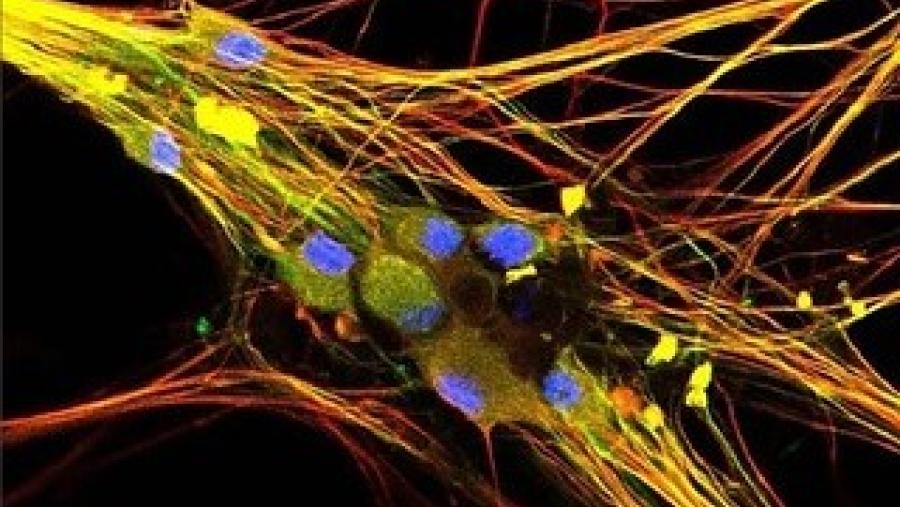

Image

A molecular inventory of pain-sensing nerve cells may lead to more targeted therapies